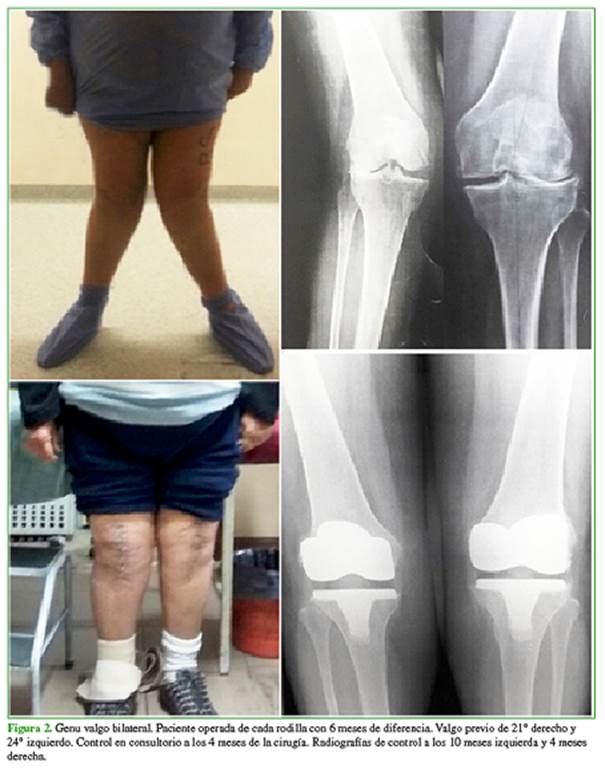

Las mediciones radiográficas de corrección del deseje fueron: ángulo femorotibial preoperatorio promedio: valgo 27º (rango 21-39) y ángulo femorotibial posoperatorio promedio: valgo 6,2º (rango 4-10) (Figuras 1 y 2).